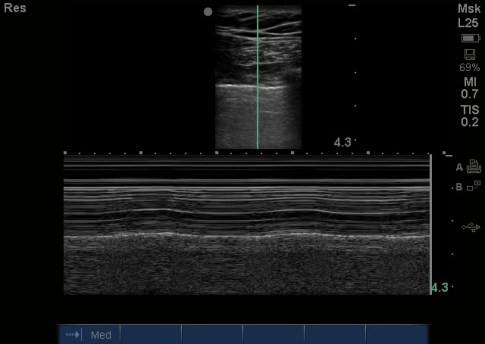

That left side had no lung sliding and a stratosphere sign on M Mode, that’s the first thing that Dr. Chough appreciated, but it was also unclear as to why it was so echogenic (gray) beneath the pleural line. He had no signs of tension pneumothorax on clinical exam, so instead of performing a needle thoracostomy and chest tube, she aborted the rest of the RUSH and ordered a stat Chest XR:

Given the above findings of a dilated aortic knob and correlating that to the small pericardial effusion, left sided pleural effusion, and clinical findings, she realized what she was seeing was a ruptured ascending thoracic aneurysm (with blood entering the pericardial space and the leaking blood collecting on the left side of his chest – as the aorta is situated on the left side and that’s where blood will go). His HR remained between 55-65 and his BP remained between 70s-100s with normal mentation. A stat CT angio of his chest was ordered and cardiothoracic surgery was called. As I dont usually provide CT images, this one was an interesting one and explained why Dr. Chough saw gray on the left anterior chest beneath the pleural line:

It was clotted blood adjacent to the 6×6 cm saccular thoracic aneurysm that started distal to his left subclavian artery. It was a good thing she didnt stick a needle in that, relied on her physical exam, and correlated her US findings to it. The radiologists states that this aortic rupture likely occurred a couple days earlier, with clot formation in the left chest and around the aortic knob but with continued leaking of blood. It’s amazing this guy is still alive! The surgeons debated on whether to take the patient to the cath lab versus the OR due to his prior surgery and possible scarring, and finally took him to the OR where he ad endovascular aortic repair and is doing well today.